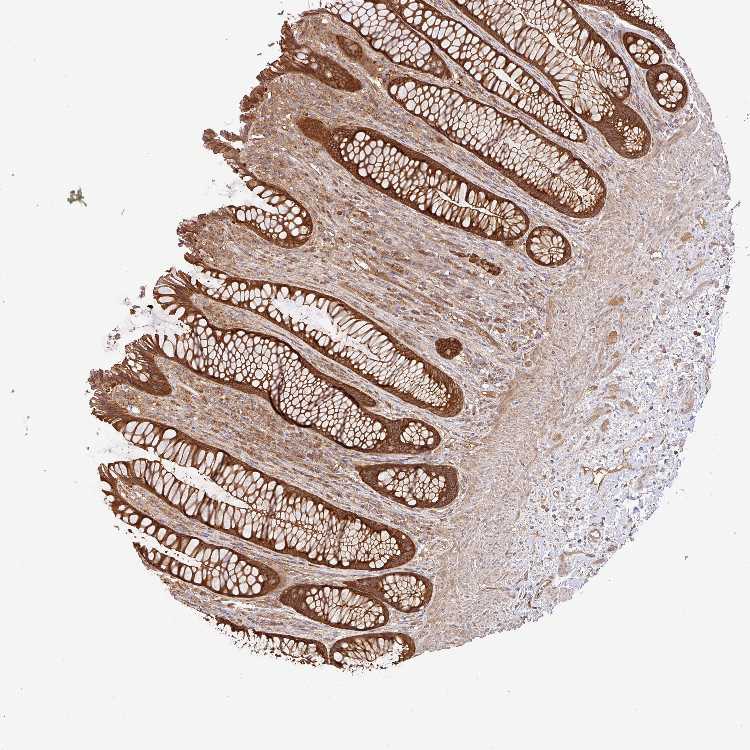

RECTUM - Antibody stainingi

Antibody staining in the annotated cell types in the current human tissue is reported as not detected, low, medium, or high, based on conventional immunohistochemistry profiling in selected tissues. This score is based on the combination of the staining intensity and fraction of stained cells. Each image is clickable and will lead to virtual microscopy that enables deeper exploration of all samples and also displays staining intensity scores, fraction scores and subcellular localization as well as patient and tissue information for each sample.

Ascending and descending describe two types of gradient, based on difference in staining intensity between enterocytes in crypts and apical enterocytes.

Ascending - the staining intensity is stronger in apical enterocytes (towards the lumen) compared to enterocytes in the crypts (gland based)

Descending - the staining is weaker in apical enterocytes compared to enterocytes in crypts

Antibody HPA052488

Glandular cells High